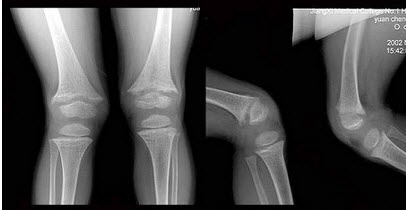

女,42岁,双下肢疼痛,结合图像,最可能的诊断是()

A.Paget病

B.内生软骨瘤

C.非骨化性纤维瘤

D.骨巨细胞瘤

E.骨纤维异常增殖症